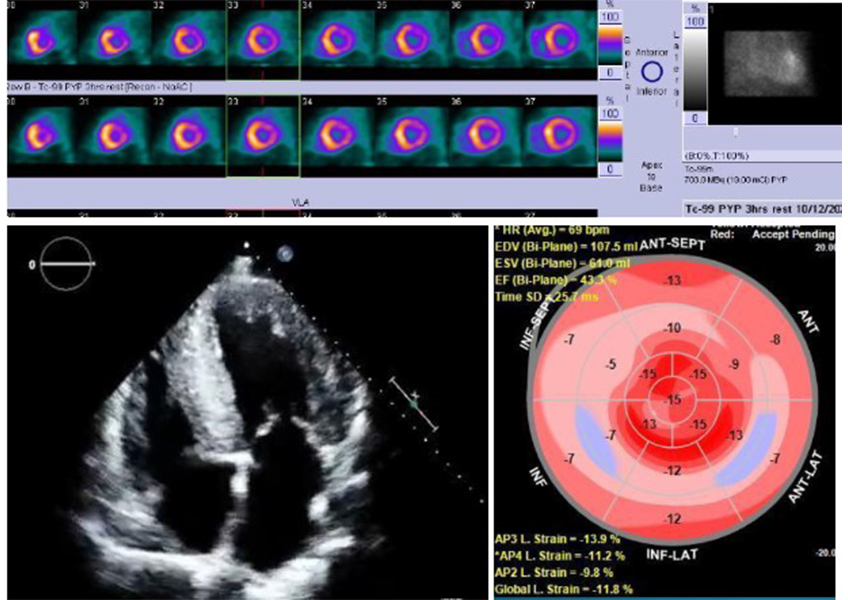

Today, diagnosis is based on an algorithm factoring in EKGs and echocardiograms, blood work to exclude other conditions, and confirmation with cardiac MRI and nuclear imaging to pinpoint protein deposits in tissues, as well as genetic testing.